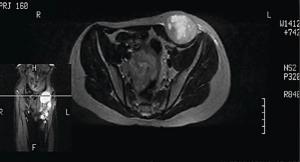

KEY POINTS • Synovial sarcomas are often mistreated with unplanned tumor resection. • Attention from specialists early in the course of SS can minimize the risk of recurrence, metastases, and the necessity for resurgery, all of which are increased with unplanned tumor resection. • Chemotherapy alone does not provide sufficient local control of the tumor. • Resurgery, in conjunction with radiotherapy and chemotherapy, is the best choice of management for this patient.